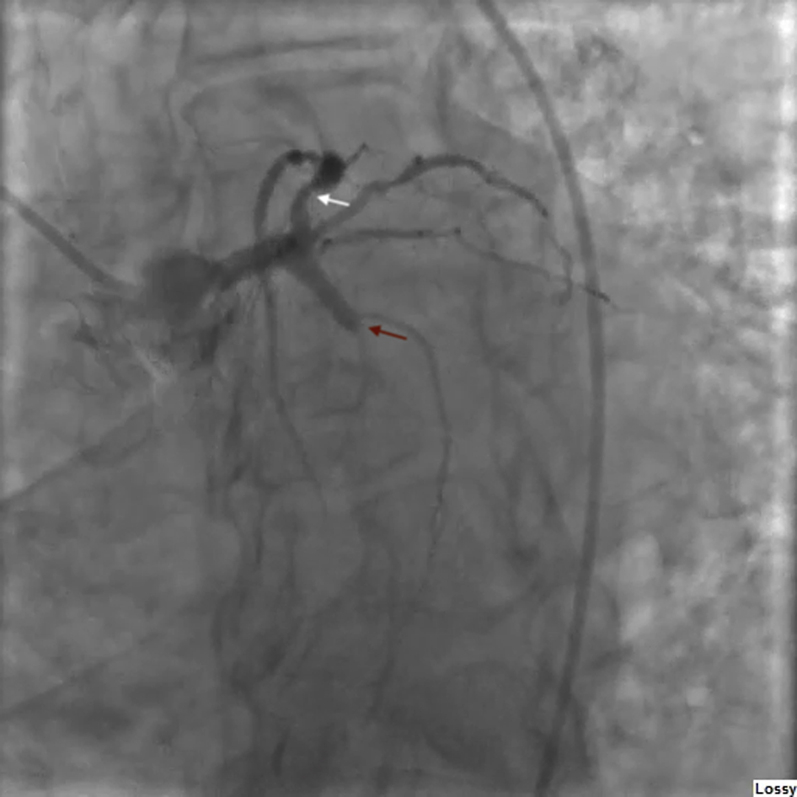

Figure 2.

Left Anterior Oblique Caudal Coronary Angiogram

Caudal left anterior oblique coronary angiogram shows a culprit 100% occlusion of the left circumflex coronary artery (red arrow) and a nonculprit left anterior descending artery with 90% proximal stenosis (white arrow).

Electrocardiography revealed a posterior ST-segment elevation myocardial infarction (STEMI) (Figure 1) for which he received tenecteplase, clopidogrel, and aspirin. He was airlifted to the authors’ hospital for coronary angiography due to ongoing chest pain and persistent ST-segment elevation. Angiography revealed a left-dominant system with a culprit 100% thrombotic occlusion of the left circumflex coronary artery and a nonculprit 90% proximally diseased left anterior descending artery (Figures 2 and 3, Videos 1 and 2). Although the present authors were able to wire past the lesion, balloon angioplasty was unsuccessful due to extensive thrombus burden.